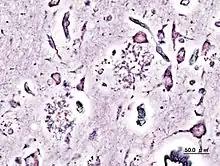

Impregnación argéntica de una biopsia de un paciente afectado de Alzheimer. Se observan placas seniles.

Tradicionalmente, se han empleado técnicas de impregnación de metales para contrastar las preparaciones para microscopía óptica. Las impregnaciones argénticas han sido especialmente precisas, como la de Golgi o Rio Hortega.